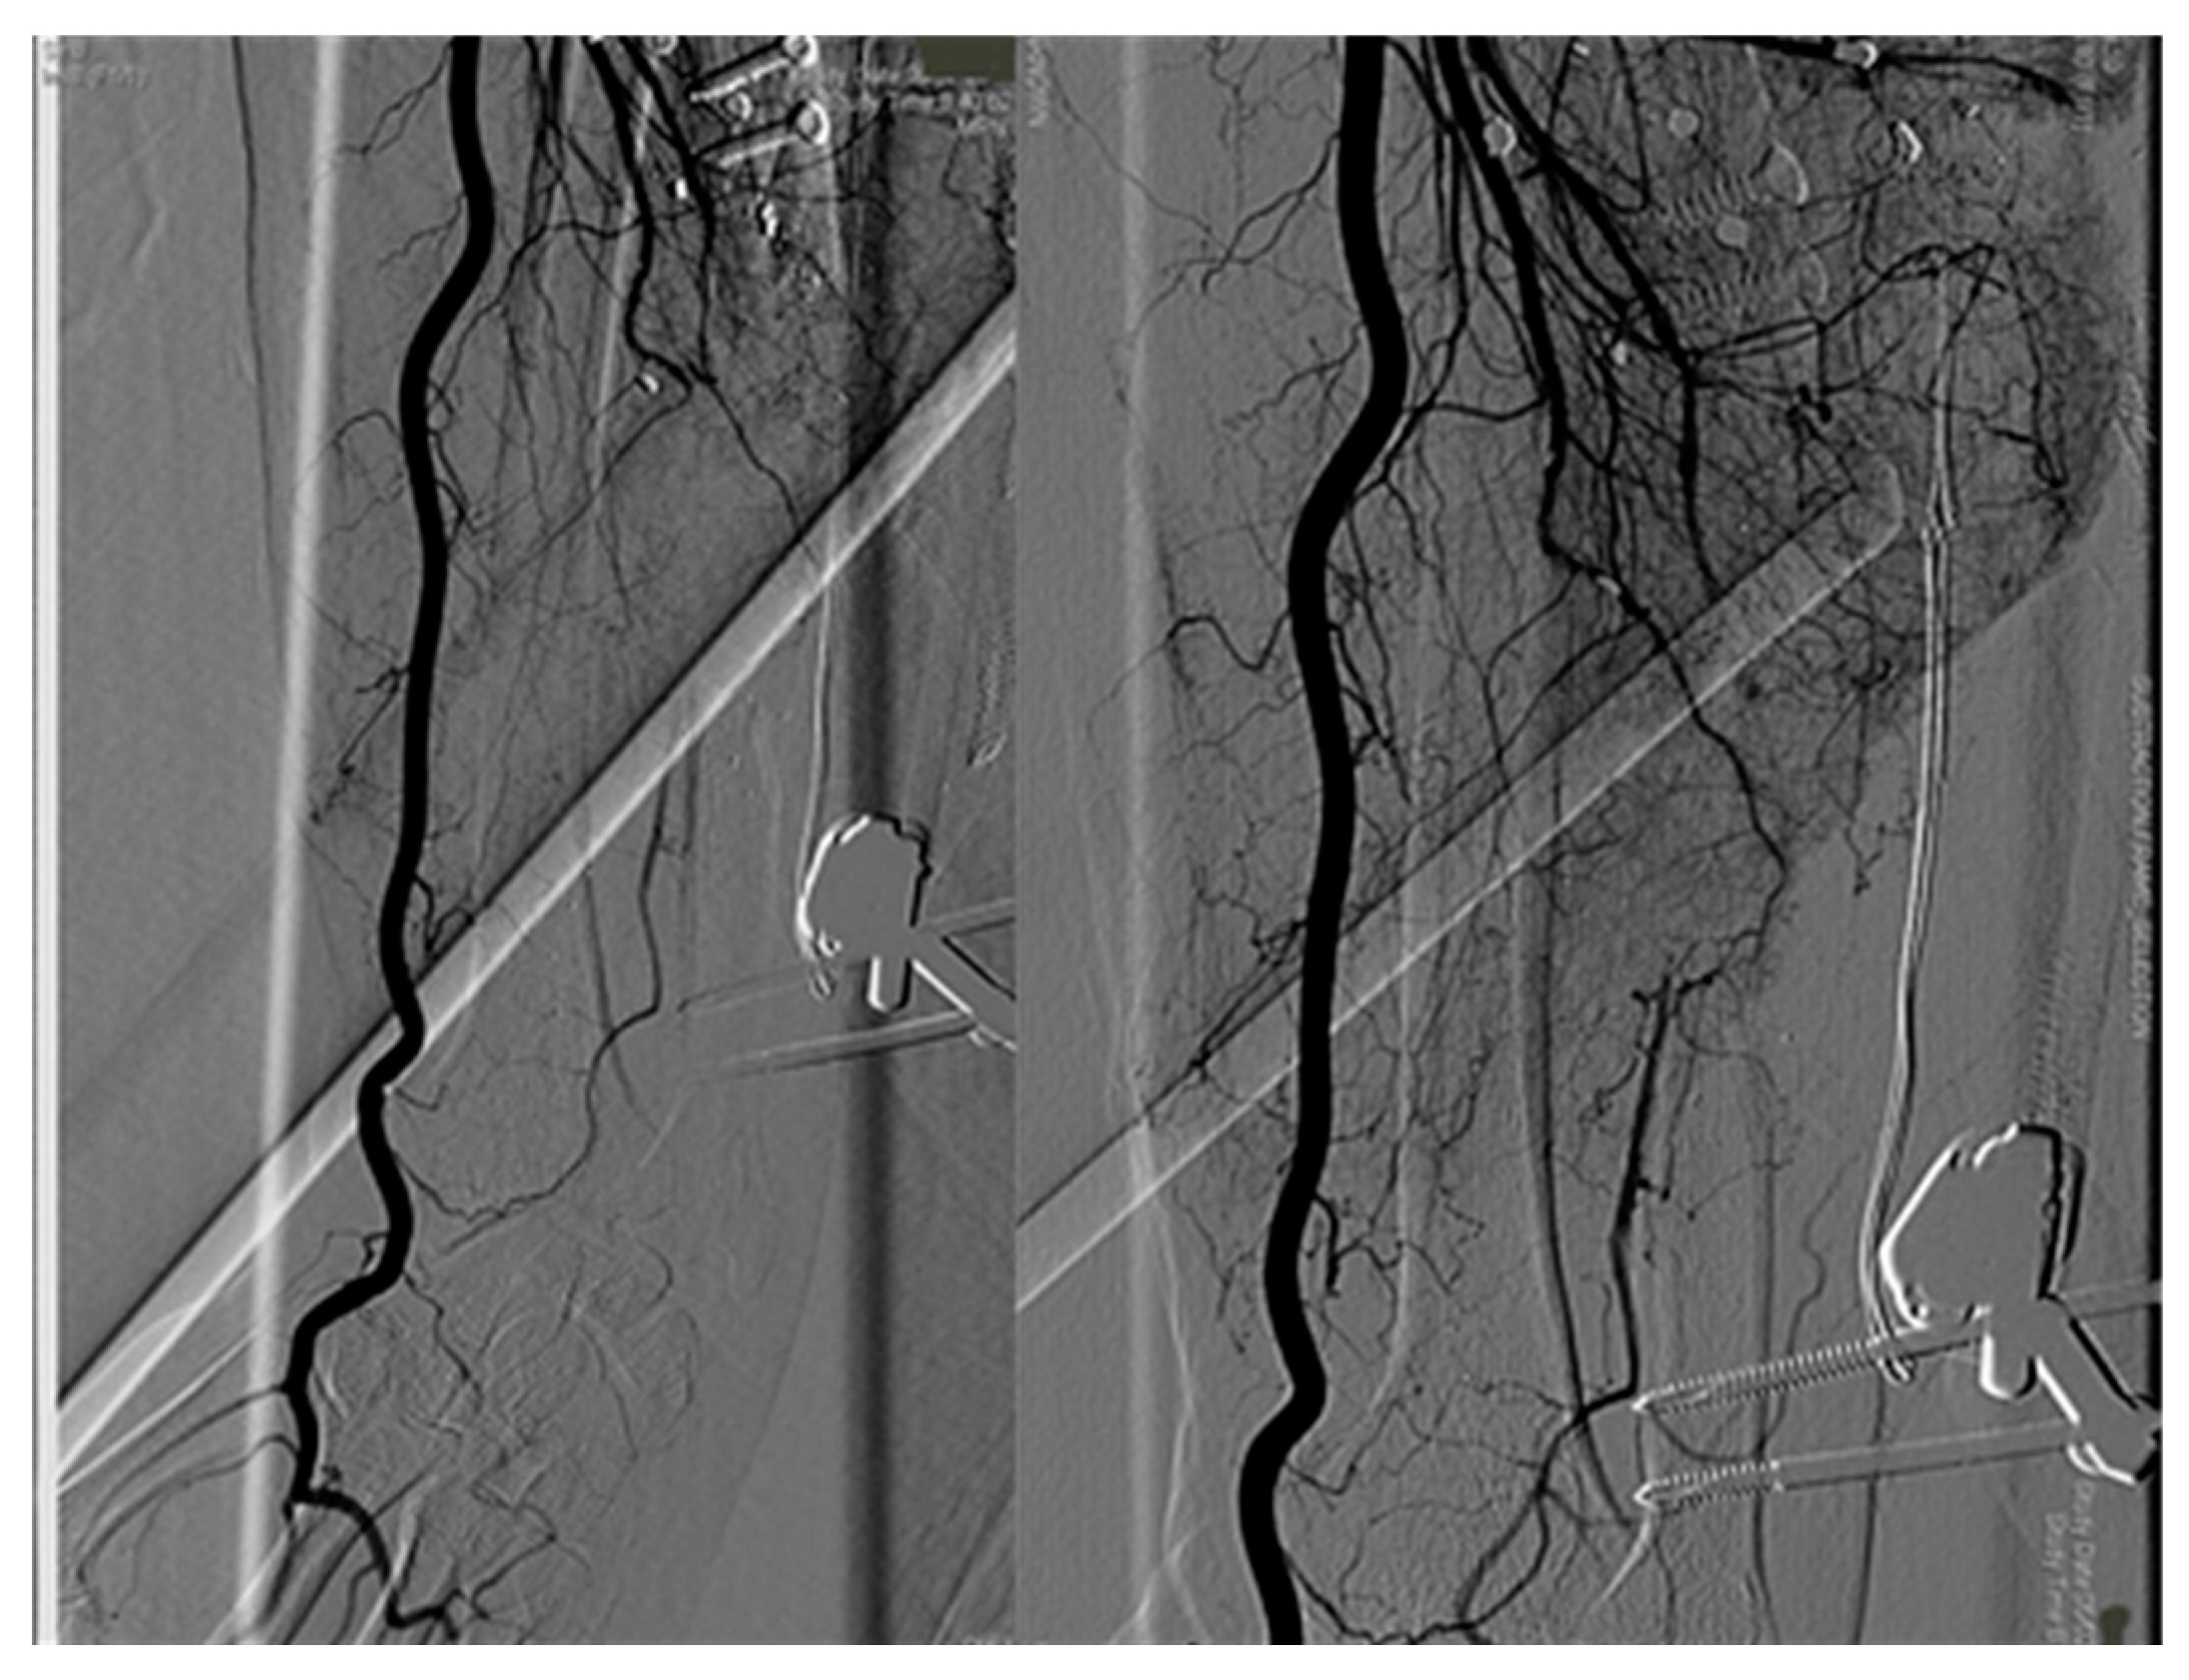

Post-operative angiography displayed only radial artery blood flow (Figure 4).

Figure 4. Angiography showed ulnar artery avulsion and interruption.